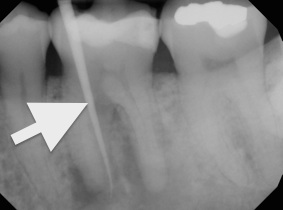

Chronic apical abscess is typically indicated by a radiograph that reveals a radiolucency. Clinically, there is a sinus tract present on the gingival tissue. It is paramount that the draining sinus tract be traced with a gutta-percha cone and then radiographed (Figure 3 and Figure 4).

Radiographic confirmation of periradicular diagnosis—chronic apical on tooth No. 19. Note the tracing of the inserted gutta-percha to the etiology. Local anesthesia is generally not required for a sinus tract tracing.

Figure 4